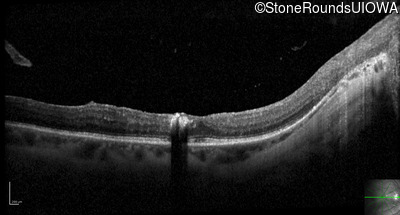

Optical Coherence Tomography - Left - 20/40 +1

Exemplar / OCT Stack